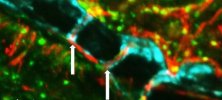

"Sekretne" kanaliki między szpikiem czaszki i mózgiem to świetny skrót dla komórek odpornościowych

28 sierpnia 2018, 12:35Nowe badanie na myszach i ludziach pokazało, że drobne kanaliki przecinające szpik kostny czaszki mogą stanowić bezpośrednie połączenie dla komórek odpornościowych reagujących na urazy spowodowane przez udar i inne zaburzenia.